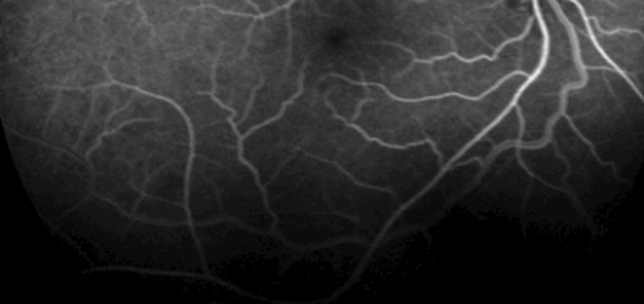

A single intravitreal bevacizumab in the treatment of breast carcinoma related choroidal metastasis

Antonio Berarducci

Inderpaul S Sian

Roland Ling

1st June 2015